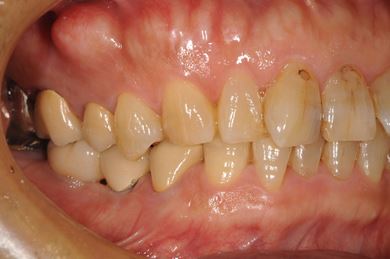

インプラントの症例写真 IMPLANT

インプラント治療+セラミック治療

| 主訴 | 部分入れ歯のバーが舌に当たるため、奥歯2本のインプラント治療を希望。 | ||||||||||||||||||||||||||||||||

| 治療方針 | 右下欠損部分をインプラント治療にて、機能的・審美的回復を行う。 | ||||||||||||||||||||||||||||||||

| 治療内容 | インプラント2本、メタルボンドセラミッククラウン8本、メタルボンドセラミック用土台6本 | ||||||||||||||||||||||||||||||||